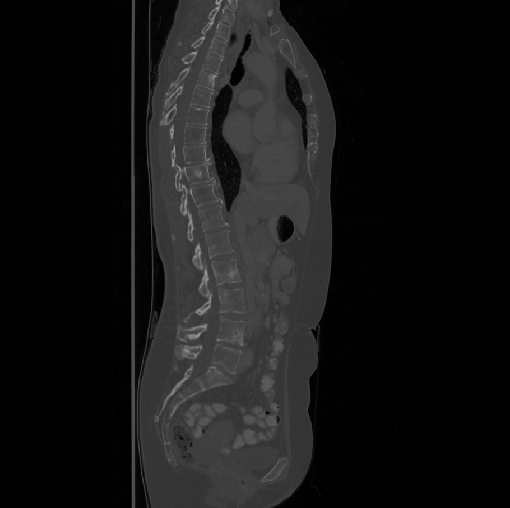

Spinal imaging via computed tomography (CT), magnetic resonance imaging (MRI), radiography, ultrasound, positron emission tomography (PET), and other radiologic imaging modalities is essential for noninvasively visualizing and assessing spinal pathology. Computational methods support and enhance a physician’s ability to utilize these imaging techniques for diagnosis, noninvasive treatment, and intervention in clinical practice. Analysis algorithms developed in the field of computer vision, computer graphics, signal processing, and machine learning have been adapted to analyze spinal images (Li et al., 2015). Conventionally, CT is preferred to study the spine due to a high bone-soft tissue contrast. There are diverse image appearance variations due to differences in vertebral position, metal artifacts and spinal diseases, etc., challenging the analysis algorithms. Fig. 1 gives some examples of these various conditions.

We calculate the two metrics of each vertebra, and the results are reported in Table 2. On the one hand, our experimental results are close to those reported in reference (Sekuboyina et al., 2020) with the same model (nnUnet), verifying the high quality of our annotations. On the other hand, Table 2 shows it is difficult to segment the diseased vertebrae (the DSC of L6 is almost 0). Specifically, the existence of L6 confuses the model, resulting in prediction dislocations (see the last row in Fig. 4). Thus, our labeled dataset, which contains many L6 cases, is very valuable for the diseased vertebrae segmentation (we have stated those cases that are hard for annotation in the readme.txt file). Table 2 illustrates that the model trained with our annotations can achieve good performance on our CTSpine1K dataset but a much worse performance on the VerSe Challenge datasets, which explains there is an obvious domain gap between our annotated dataset and the public dataset. We infer the reason is that the COlONOG dataset is based on an empty stomach and colon, confusing the deep learning model by the changes of air content in the abdomen (see Fig. 3). Therefore, our annotations are a good complement to the existing datasets.